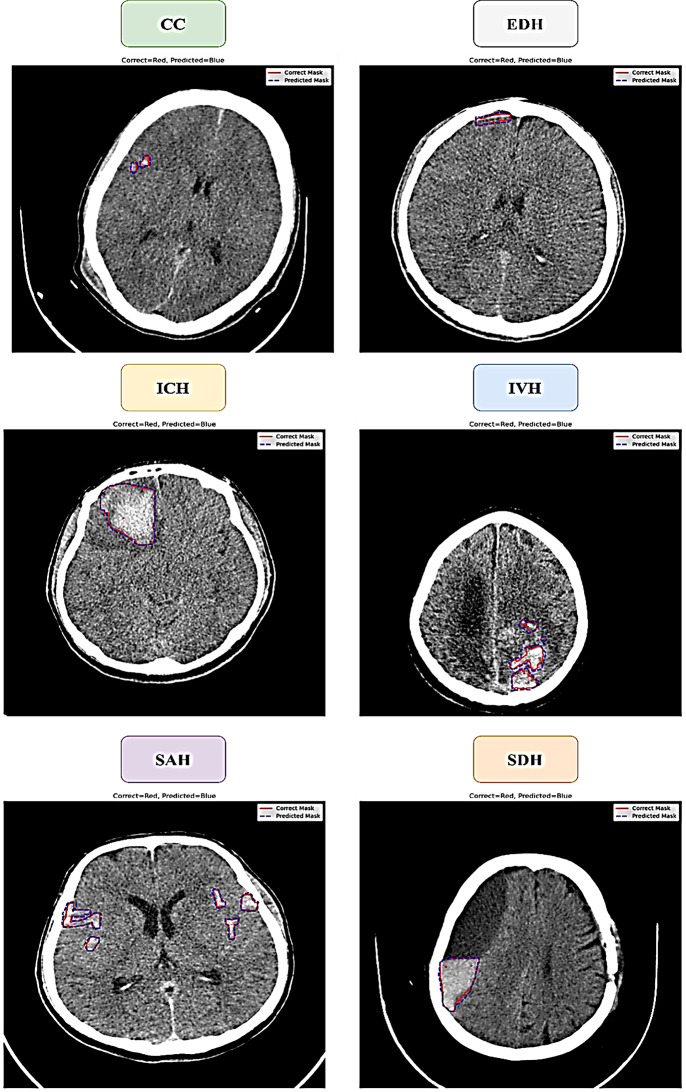

Materials and methods: A dataset of 1,347 patient CT scans was collected retrospectively, covering six types of hemorrhages: subarachnoid hemorrhage (SAH, 231 cases), subdural hematoma (SDH, 198 cases), epidural hematoma (EDH, 236 cases), cerebral contusion (CC, 230 cases), intraventricular hemorrhage (IVH, 188 cases), and intracerebral hemorrhage (ICH, 264 cases). The dataset was divided into 80% for training using a 10-fold cross-validation approach and 20% for testing. All CT scans were standardized to a common anatomical space, and intensity normalization was applied for uniformity. The ResUNet model included attention mechanisms to enhance focus on important features and residual connections to support stable learning and efficient gradient flow. Model performance was assessed using the Dice Similarity Coefficient (DSC), Intersection over Union (IoU), and directed Hausdorff distance (dHD).

Results: The ResUNet model showed excellent performance during both training and testing. On training data, the model achieved DSC scores of 95 ± 1.2 for SAH, 94 ± 1.4 for SDH, 93 ± 1.5 for EDH, 91 ± 1.4 for CC, 89 ± 1.6 for IVH, and 93 ± 2.4 for ICH. IoU values ranged from 88 to 93, with dHD between 2.1- and 2.7-mm. Testing results confirmed strong generalization, with DSC scores of 93 for SAH, 93 for SDH, 92 for EDH, 90 for CC, 88 for IVH, and 92 for ICH. IoU values were also high, indicating precise segmentation and minimal boundary errors.